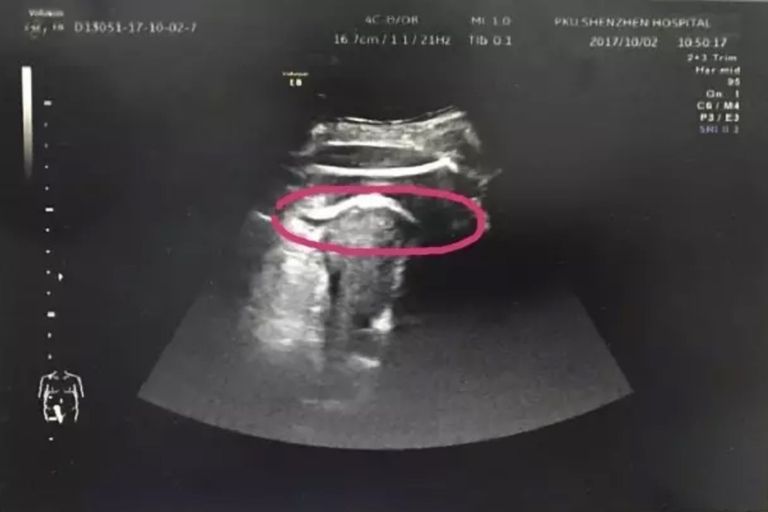

Urodzona 1 lutego 1985 roku Casey wzięła z Andrew ślub w 2015 roku. Podczas starań o dziecko i procedury in vitro w 2019 roku kobieta dowiedziała się, że ma raka jajnika III stopnia. Rok później usunięto jej organy, w których odkryto przerzuty: macicę, część śledziony, wątroby i płuc.